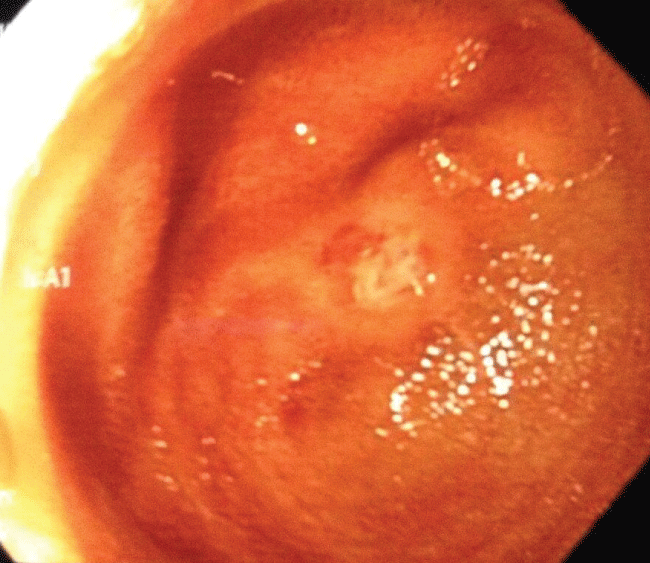

Computed tomography (CT) of the abdomen and pelvis in February 2013 showed mild splenomegaly, mesenteric lymphadenopathy, diffuse sclerosis of the bones, and with mild thickening of the distal colon. Colonoscopy was normal to the terminal ileum. Video capsule endoscopy in April 2013 showed mid-jejunal ulcerations and stenosis. The capsule did not pass into the cecum. His most recent X-ray showed that the capsule was retained. CT enterography on May 7, 2013 showed less than optimal distention of the small bowel proximally, but with an apparent wall thickening of the jejunum in the left mid abdomen with areas of mucosal hyperemia in the ileum and the retained video capsule. Ten days later, a laparotomy with intraoperative enteroscopy (Figure 1 and Figure 2) revealed six tight ulcerated stenoses within a 45cm segment at approximately 120-140 cm from the ileocecal valve. The capsule was stuck at the second stricture. Intra-operative endoscopy was unsuccessful due to the tight and firm strictures. Approximately 45 cm of small bowel was resected.

Figure 2: The gross finding of the resected specimen. It showed multiple fibrous stenoses and ulcers.

Post-operatively, he tolerated a full diet without abdominal bloating. At follow-up, iron was 25 but his ferritin was normal. Pathology revealed multifocal ulcerous stenosing enteritis as reviewed by 3 pathologists. Post-operative infliximab was started as an attempt to preclude recurrent inflammation. However, due to the poor response, it was switched to adalimumab. He was also treated with rifaximin for small intestinal bacterial overgrowth. He has improved remarkably with lessened iron infusion requirement and is now having 1-2 bowel movements a day.

The clinicopathological features of CMUSE have been summarized as follows: (1) chronic iron-deficiency anemia due to small intestinal occult blood loss, (2) rarely diarrhea, malabsorption, hematochezia or fever, (3) unexplained small intestinal strictures found in adolescent and middle-aged subjects, often requiring multiple resections of the small bowel, (4) multiple superficial ulceration of the mucosa and submucosa, predominantly in the ileum (the terminal ileum is usually spared) with infiltration of plasma cells, lymphocytes, and eosinophils, (5) a chronic or relapsing clinical course, even after surgery, (6) no biological signs of systemic inflammatory reaction, C-reactive protein (CRP) and other acute inflammatory reactants remain within normal limits or slightly increased, and (7) beneficial effect of systemic glucocorticosteroids [3,4,7]. Our patient was presented with chronic anemia with melena and recurrent abdominal pain. No diarrhea, malabsorption, hematochezia or fever was documented. His small bowel resection for the strictures with intraoperative enteroscopy revealed six tight ulcerated stenoses. The capsule endoscopy was found to be retained at the second stricture.